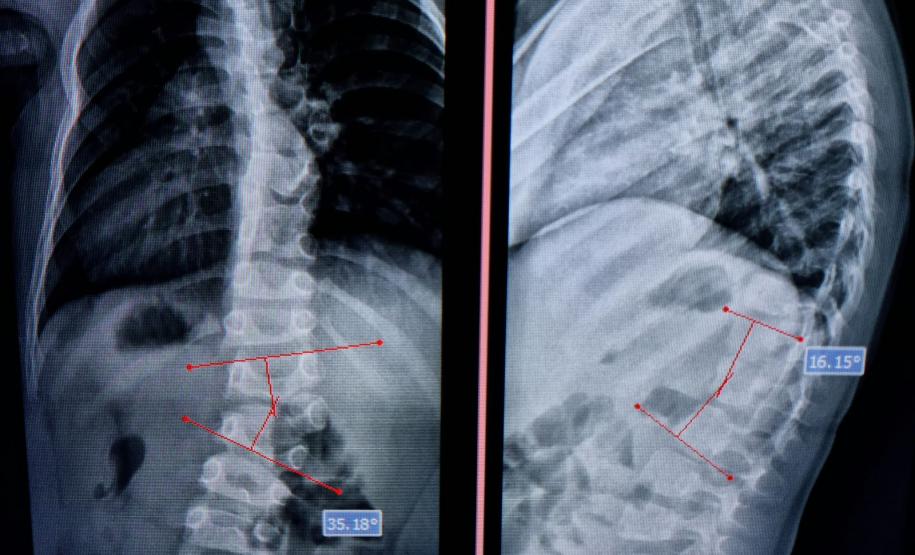

Com curvatura acima dos 100 graus, desconfortos respiratórios como falta de ar e asma, a posição do adolescente na cadeira de rodas estava bem limitada. Para a mãe de Lucas, Daniele de Oliveira Batista, a cirurgia foi fundamental para melhorar a autonomia e qualidade de vida do filho.

“Foi um longo processo até chegar aqui no CHT, esperávamos por essa cirurgia há mais de dois anos e, depois de tantas dificuldades, hoje conseguimos fazer um passeio sem que ele reclame de dor. Ele também já consegue ficar em muitas outras posições que antes eram desconfortáveis e geravam muita dor. Só temos a agradecer a toda equipe médica pelos cuidados e ótimo atendimento prestado ao meu filho”, disse.